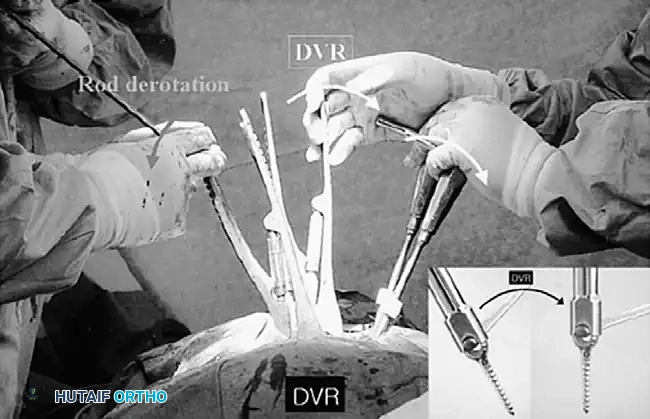

Posterior Surgeries for Idiopathic Scoliosis: A Masterclass in Surgical Technique

Associated Surgical & Radiographic Imaging